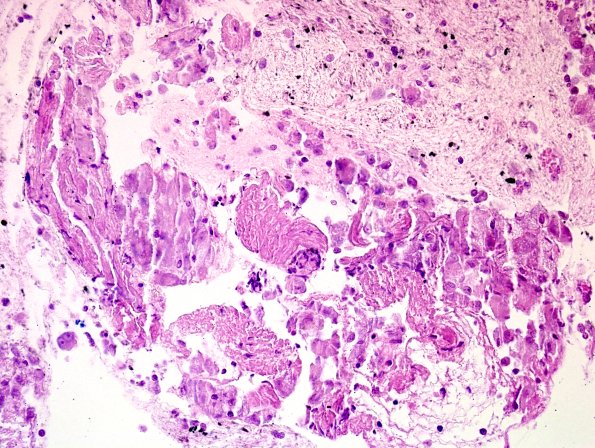

An endobronchial ultrasound-guided fluoroscopy assisted fine needle aspiration of a lung lesion showed non-necrotizing granulomatous inflammation without fungal or AFB organisms. (H&E)